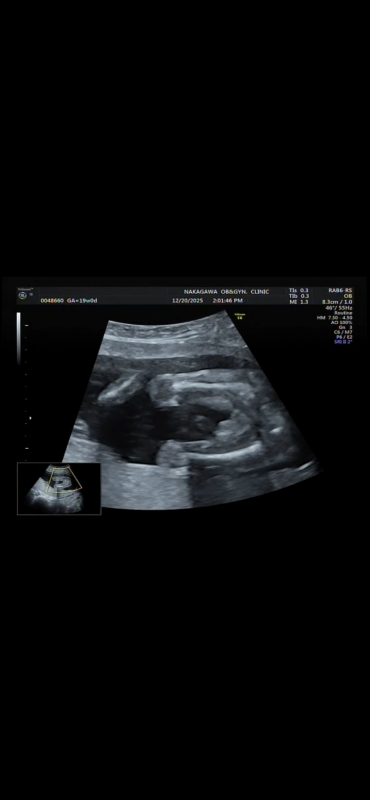

19週になりましたが、まだ性別がわかりません。 正月に家族とも話したいなーと思っているのですが 次の検診が年明けなので もし分かるのであれば教えて欲しいです!

へその緒が近くにあるのでわかりづらく、、

確定はできないのはわかっていますが多分どっちかでも知りたいです、、!

お腹の赤ちゃんの性別についてですね。

添付をしてくださった画像を拝見いたしました。

男の子のシンボルとなりそうなものがありそうに見えあたり、なさそうにも見えたりと、どちらかということもお返事がしにくい状況でした。

せっかくご相談いただいていたのに、大変申し訳ありません。

次回の健診の時に、ご確認いただけたらと思います。